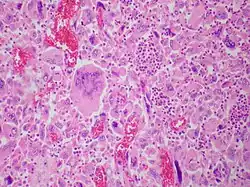

| Pulmonary giant cell carcinoma represents a rare variety of non-small cell lung carcinoma that is characterized by the presence of numerous tumor giant cells and an influx of inflammatory cells that are mostly polymorphonuclear leukocytes admixed with macrophages. The dense oval aggregates of polymorphonuclear leukocytes seen in this image are probably located in the cytoplasm of tumor giant cells (emperiopolesis) that have been sectioned in a plane that does not include their nuclei. | |

Both "tumor cell-tumor cell" and "leukocyte-tumor cell" emperipolesis (i.e. active penetration of the latter by the former) is very commonly seen in cases of GCCL.[12]